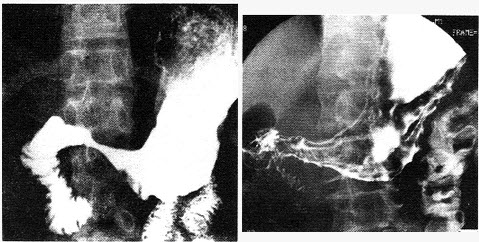

�����У�58�ꡣ��������2�����࣬X��ͼ�����£����п��ܵ�����ǣ���

A.ʳ�ܰ�

B.ʳ�ܾ�������

C.ʳ�ܼ�����

D.����ʳ����

E.ʳ�ܽ��